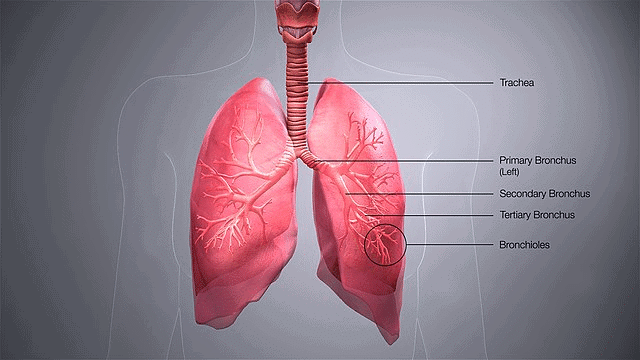

Ciliated epithelium is primarily found in the inner surfaces of hollow organs like ___ and ___. |